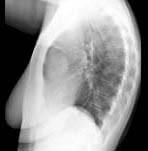

问题 根据图象提示,重症肌无力患者做X线胸片检察的目的是 ( )

选项 A、检察是否有膈肌麻痹 B、检察是否有胸腺瘤 C、检察是否有异位甲状腺 D、检察是否有肺结核 E、检察是否合并有肺部感染 一、单项选择题

答案 B